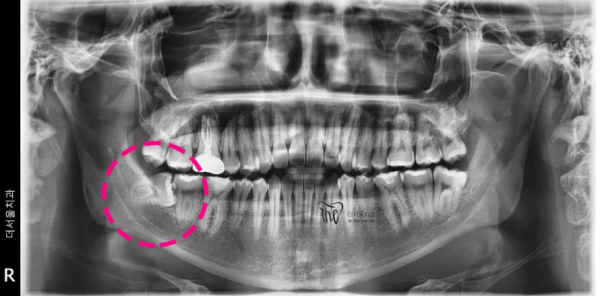

6494f584fbb6daadf023d7b84fd247d6_1679151741_061.png

이렇게 누워있는 사랑니는 발치를 하는것이 매우 어렵고

신경써야 하는 부분이 많기 때문에 엑스레이촬영을 자세히 하여

신경관과 뿌리의 거리를 확인하고 발치계획을 세우게 됩니다.

신경과 치아뿌리를 정확히 확인하기 위해서

CT촬영을 하여 확인합니다. 자세히 확인을 해 보니

이 환자분의 경우 약 2mm 정도의 거리가 있어 발치를 할 수 있었습니다.

신경과 가까운 위치의 사랑니발치를 잘못하면

안면마비등의 다양한 부작용이 발생할 수 있기 때문에

신중한 발거를 해야 합니다.

이렇게 누워있는 사랑니는 바로 앞에 있는 어금니가 있기 때문에

치아를 쪼개서 발치를 하게되었습니다.